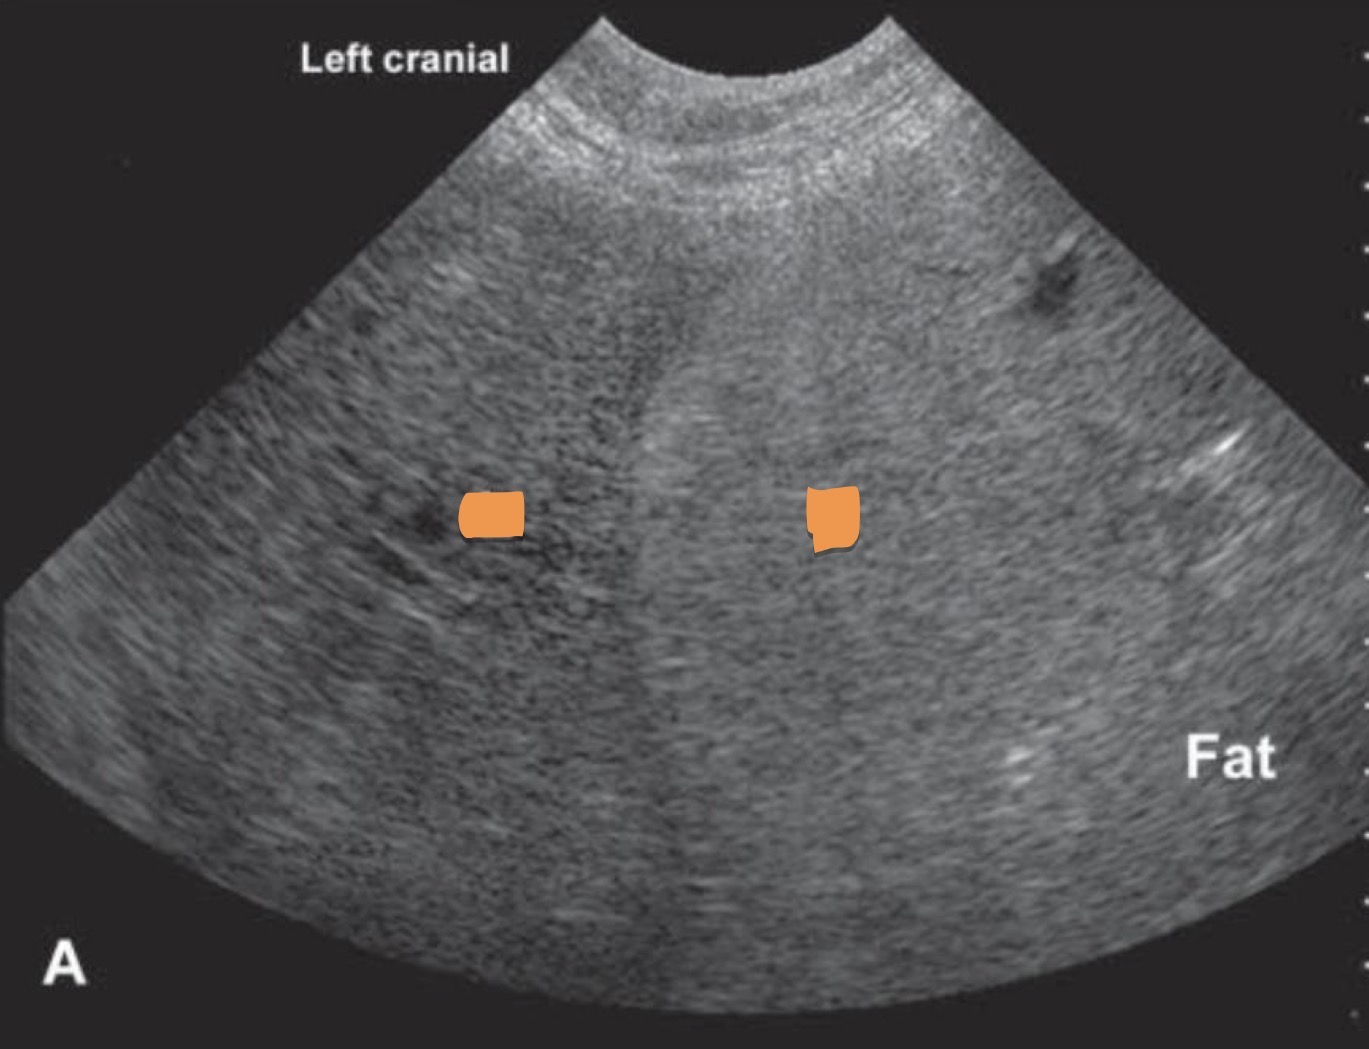

Left gall bladder

Right liver

What organs are marked?